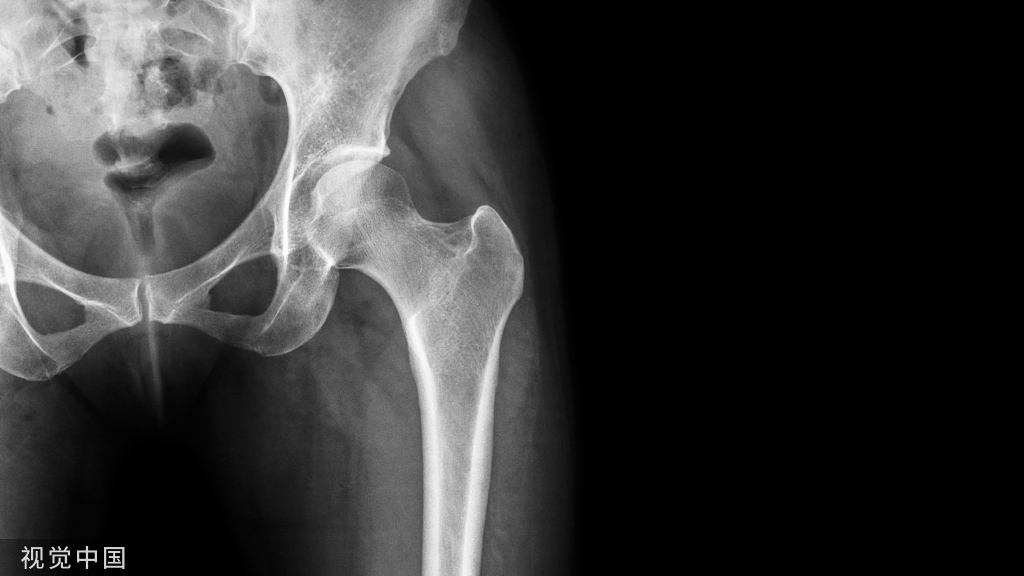

肱骨髁上骨折是最常见的儿童肘部骨折,大约占全部肘关节损伤的50%~70%,常见于3~10岁的儿童。是儿童肘部的严重型损伤,如果治疗不当,并发症发生率会很高。

3  小儿肘关节骨折,髁上骨折70%

小儿肘关节骨折的70%

好发年龄5~8Y